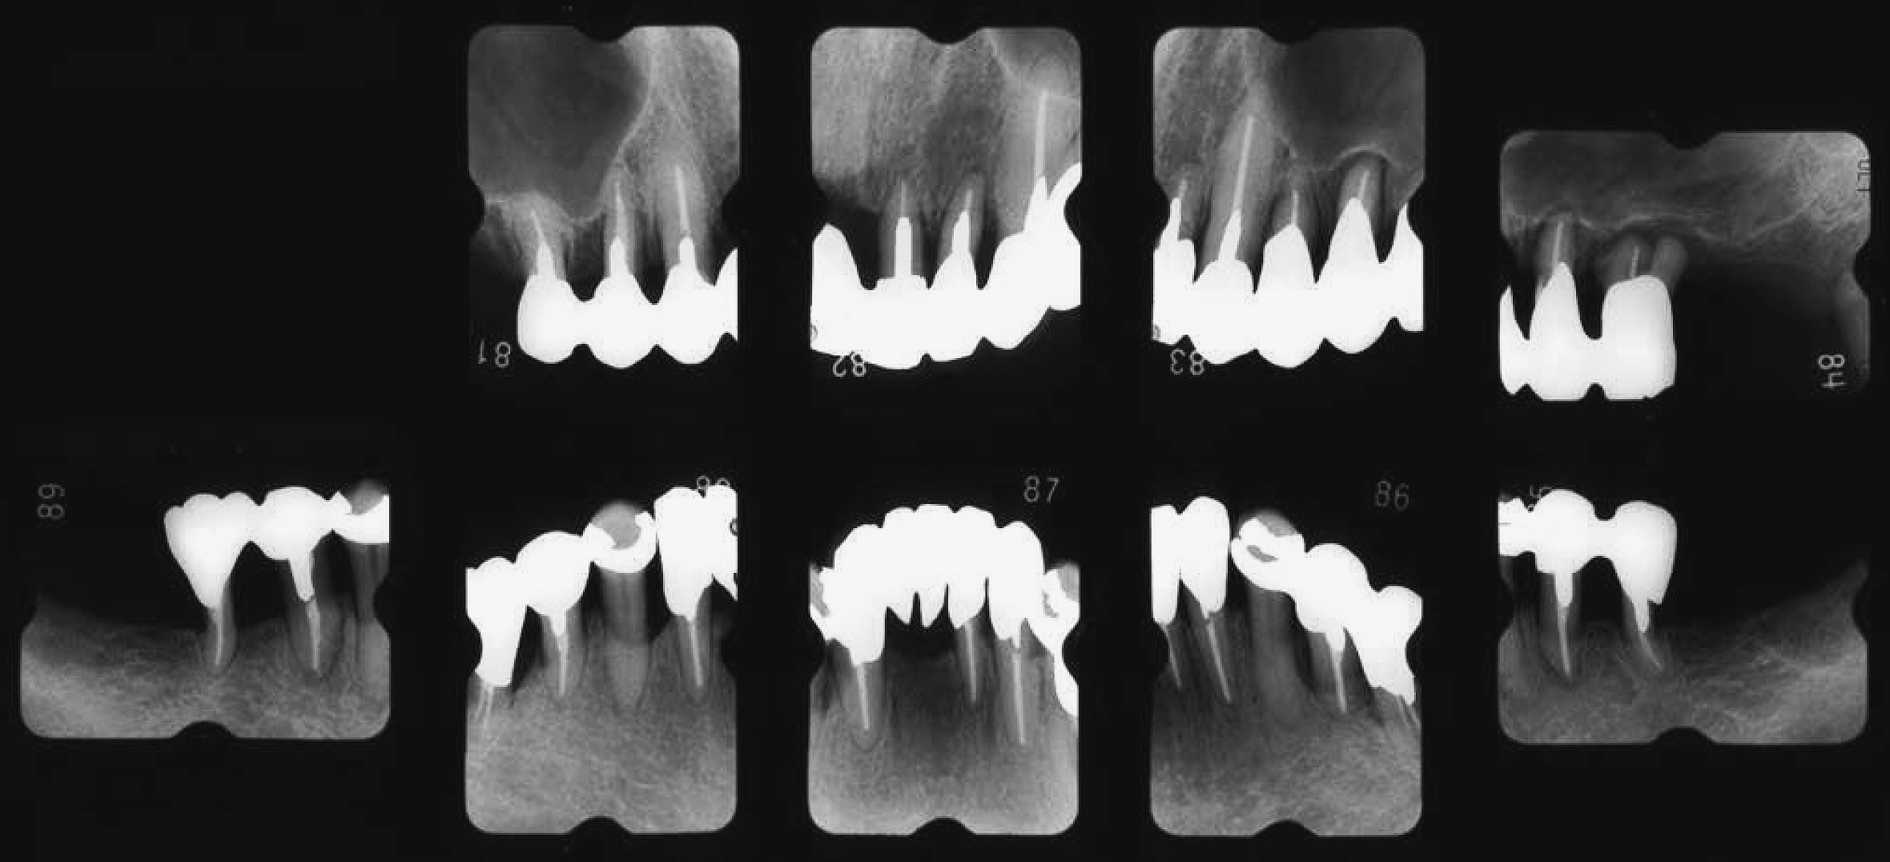

b) 治療方針と治療計画広汎型重度慢性歯周炎で喫煙関連性歯周炎でもある(図2,図3)。市場でご主人と天ぷらを揚げて販売している。仕事が多忙で,毎日疲労感が強く,睡眠も十分に取れない。重大な悩み事を持っている(内容不明)。細身体で,明らかにタバコ臭がある。歯周組織検査後,病状の説明を行い,治療計画を説明した。その際,希望があれば「禁煙指導」をする旨伝えたが,受諾はなかった。当時(平成6年)は現在ほど禁煙キャンペーンに熱心ではなかったことも災いしている。しかし,歯肉退縮,年齢42歳でかなりやせ型,タバコ臭と喫煙の悪影響がみられ,深いポケット残存部へのフラップ手術も計画しづらく,また再発の危険性も高いため,プラークコントロールレベルの改善に加えて禁煙達成を歯周外科手術実施の条件として計画を立てた。患者から得られた情報は歯周組織所見(図2)として歯根露出(歯肉退縮),歯の挺出,歯の着色,歯石沈着等であった。歯肉に発赤・腫脹の炎症所見が認められる。同様に,エックス線写真(図3)より,全顎的に高度な歯槽骨吸収がみられ,37および47は既に欠損し,17,16,12,11,22,24,25,26,27,31,41,42はほぼ根尖に至る骨吸収像,上下大臼歯はすべて根分岐部病変に罹患していることが分かった。

初診時(42歳,女性)のエックス線写真。